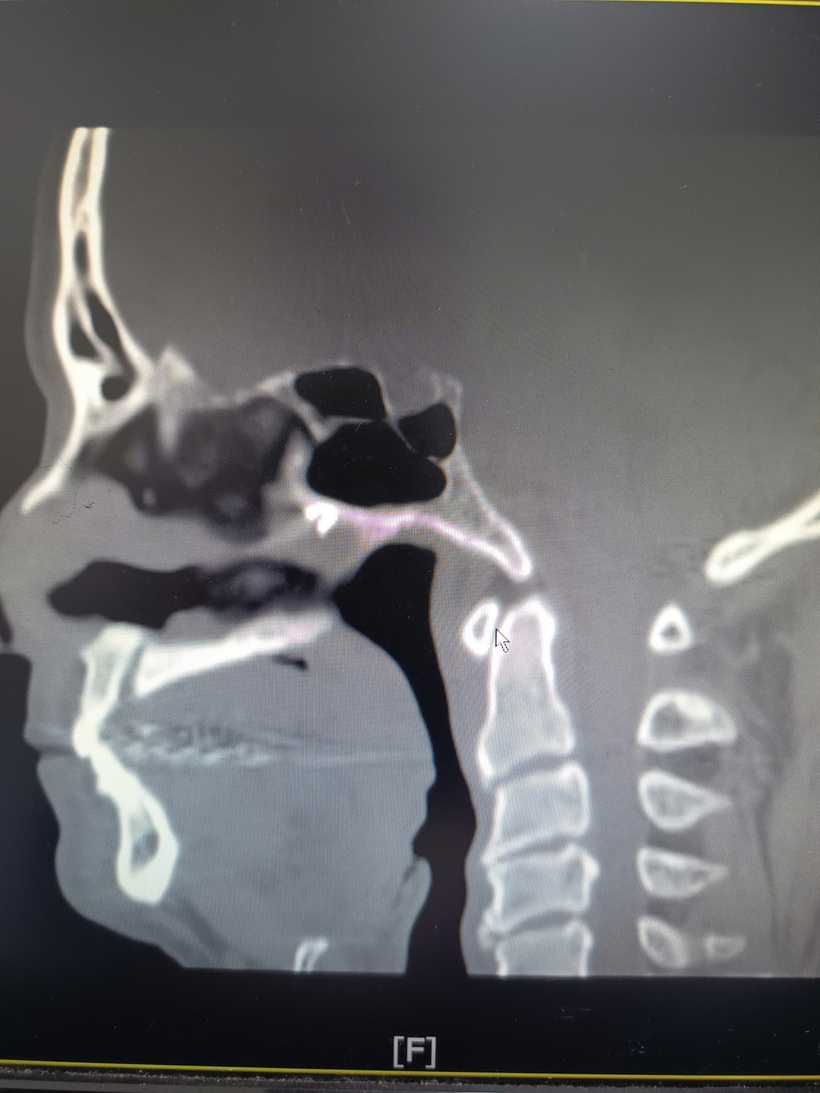

Tại lần thăm khám này, bệnh nhân được chỉ định nội soi tai mũi họng và chụp cắt lớp vi tính (CLVT) xoang. Kết quả nội soi cho thấy vách ngăn mũi bị thủng, niêm mạc biến đổi mạn tính. Đặc biệt, hình ảnh CLVT phát hiện một dị vật cản quang nằm ở phần sau, trên của vách ngăn mũi phải, cách cửa mũi trước khoảng 7 cm, sát mặt trước xoang bướm.

Theo các bác sĩ, kết quả CLVT đóng vai trò then chốt, giúp xác định chính xác vị trí dị vật, nguyên nhân gây viêm mạn tính kéo dài và các cơn đau đầu dai dẳng của bệnh nhân trong nhiều năm.

Dị vật nằm sâu, sát vùng trước xoang bướm, vị trí khó tiếp cận. Ảnh: BVCC